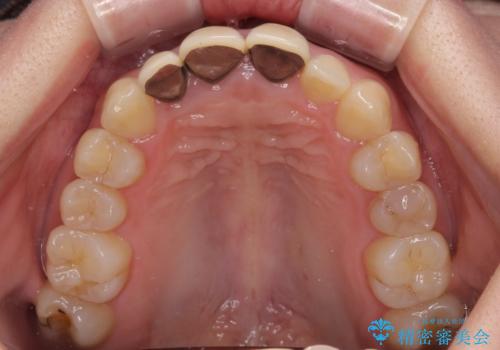

- 以前に装着した前歯のクラウンの縁が見えていることを気にして来院された患者様です。

根尖部に病変のある2歯は事前に根管治療を行い、オールセラミッククラウンにて補綴することとしました。